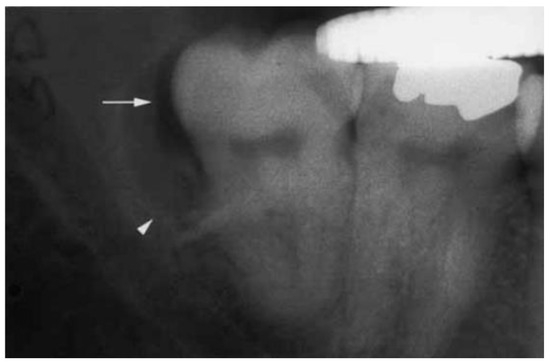

4.2. PCs of Mandibular Third Molars

4.2.2. Radiographic Features